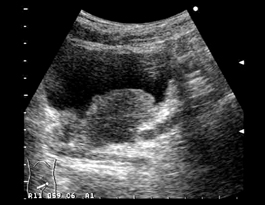

![]() 膀胱壁に乳頭状の腫瘤像がみえる。小さい腫瘍では尿潜血以外の所見を認めず、偶然見つかるケースも多い。膀胱内の尿量が不充分だと収縮した膀胱壁に隠れてしまう所見である。 |